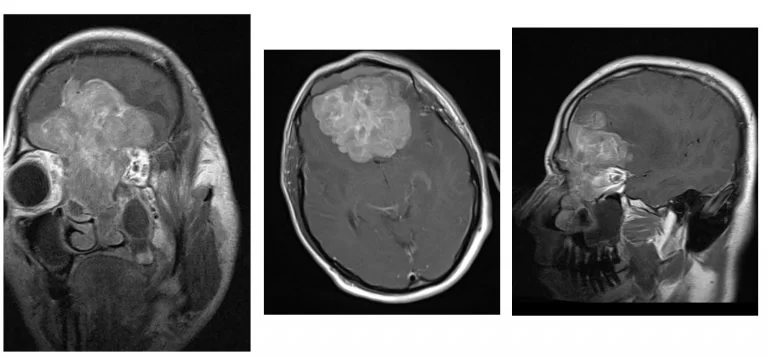

Ασθενής άνδρας, 44 ετών με διαταραχές προσωπικότητας, κεφαλαλγίες και ανοσμία. Επείγουσα εισαγωγή λόγω απώλειας όρασης και βυθιότητας.

Η αξονική και μαγνητική τομογραφία εγκεφάλου ανέδειξε γιγαντιαία εξεργασία στον πρόσθιο κρανιακό βόθρο με σημαντική επέκταση εντός της ρινικής κοιλότητας και διήθηση των οφθαλμικών κόγχων, κυρίως αριστερά.

Ο ασθενής υπεβλήθη σε αμφιμετωπιαία κρανιοτομία καθώς επίσης και σε ενδοσκοπική διαρρινική αφαίρεση της βλάβης. Η ιστολογική εξέταση ανέδειξε αισθησιονευροβλάστωμα.

Μετεγχειρητικά σαφής βελτίωση της όρασης και των λοιπών συμπτωμάτων.

Ο συγκεκριμένος όγκος είναι εξαιρετικά εκτεταμένος και αποτελεί σε κάθε περίπτωση μια χειρουργική πρόκληση. Ο συνδυασμός κρανιοτομίας και ενδοσκοπικής διαρρινικής προσπέλασης επέτρεψε την αφαίρεση της βλάβης. Σε περιπτώσεις σαν και αυτή, το έλλειμα στη βάση του κρανίου μετά την αφαίρεση του όγκου είναι ιδιαίτερα εκτεταμένο και πρέπει να υπάρχει σαφές σχέδιο αποκατάστασης της βάσης του κρανίου με συνδυασμό αυτόλογων και ετερόλογων μοσχευμάτων.